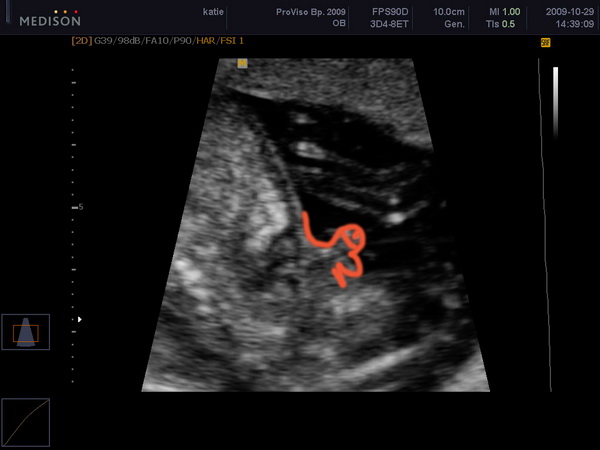

Íme egy fotó, Kedves beleművészkedett, hogy egyértelműbb legyen. Engem egy kedves indiai nőce vizsgált, ő volt a tanító, és ketten vizsgálódtak még. Sokáig nézte a szívét, azt mondta, hogy olyan szülészorvost keressek, aki tudja követni a baba szívét, mert valami olyat észlelt, hogy aszinkronocitás van, nem nagy baj, csak valami nem pont egyszerre működik.....nem egyszerre húzódik össze, vagy valami ilyesmi... Kép

Kép